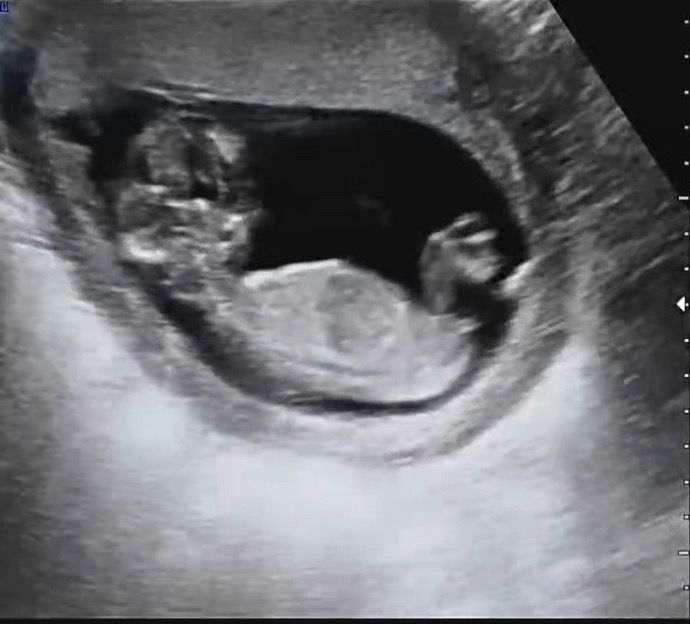

지금 각도로는 여아같아요!

각도법은 어떻게 보나요?

다들 각도법 말씀하시는데.. 봐도봐도 모르겠네요. 고수님들 어떻게 보시는지??